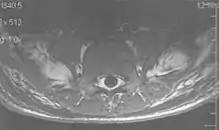

Flow

Flow can manifest as either an altered intravascular signal (flow enhancement or flow-related signal loss), or as flow-related artifacts (ghost images or spatial misregistration). Flow enhancement, also known as inflow effect, is caused by fully magnetised protons entering the imaged slice while the stationary protons have not fully regained their magnetization.[1] The fully magnetized protons yield a high signal in comparison with the rest of the surroundings. High velocity flow causes the protons entering the image to be removed from it by the time the 180-degree pulse is administered. The effect is that these protons do not contribute to the echo and are registered as a signal void or flow-related signal loss (Fig. 2).[1] Spatial misregistration manifests as displacement of an intravascular signal owing to position encoding of a voxel in the phase direction preceding frequency encoding by time TE/2.The intensity of the artifact is dependent on the signal intensity from the vessel, and is less apparent with increased TE.[1]